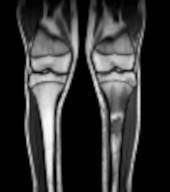

Lussazione atlanto-epistrofea e sindrome di Down: un binomio da non dimenticare

- Merli G, Marino S, Mannarà UM, Certo F, Millesoli MS, Migliore A, Testaì MA, Berto VM, La Spina M